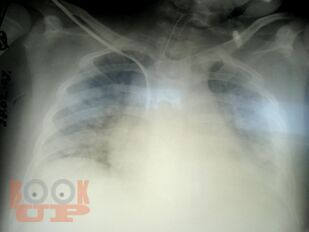

В учебно-методическом пособии представлены этиология, патогенез, клиника, осложнения, лечение, комплексная ультразвуковая, рентгенологическая, мультиспиральная компьютерная томографическая семиотика острого гематогенного остеомиелита у детей. Пособие раскрывает современные подходы ранней диагностики острого гематогенного остеомиелита у детей и предлагает оптимальный алгоритм ранней диагностики.